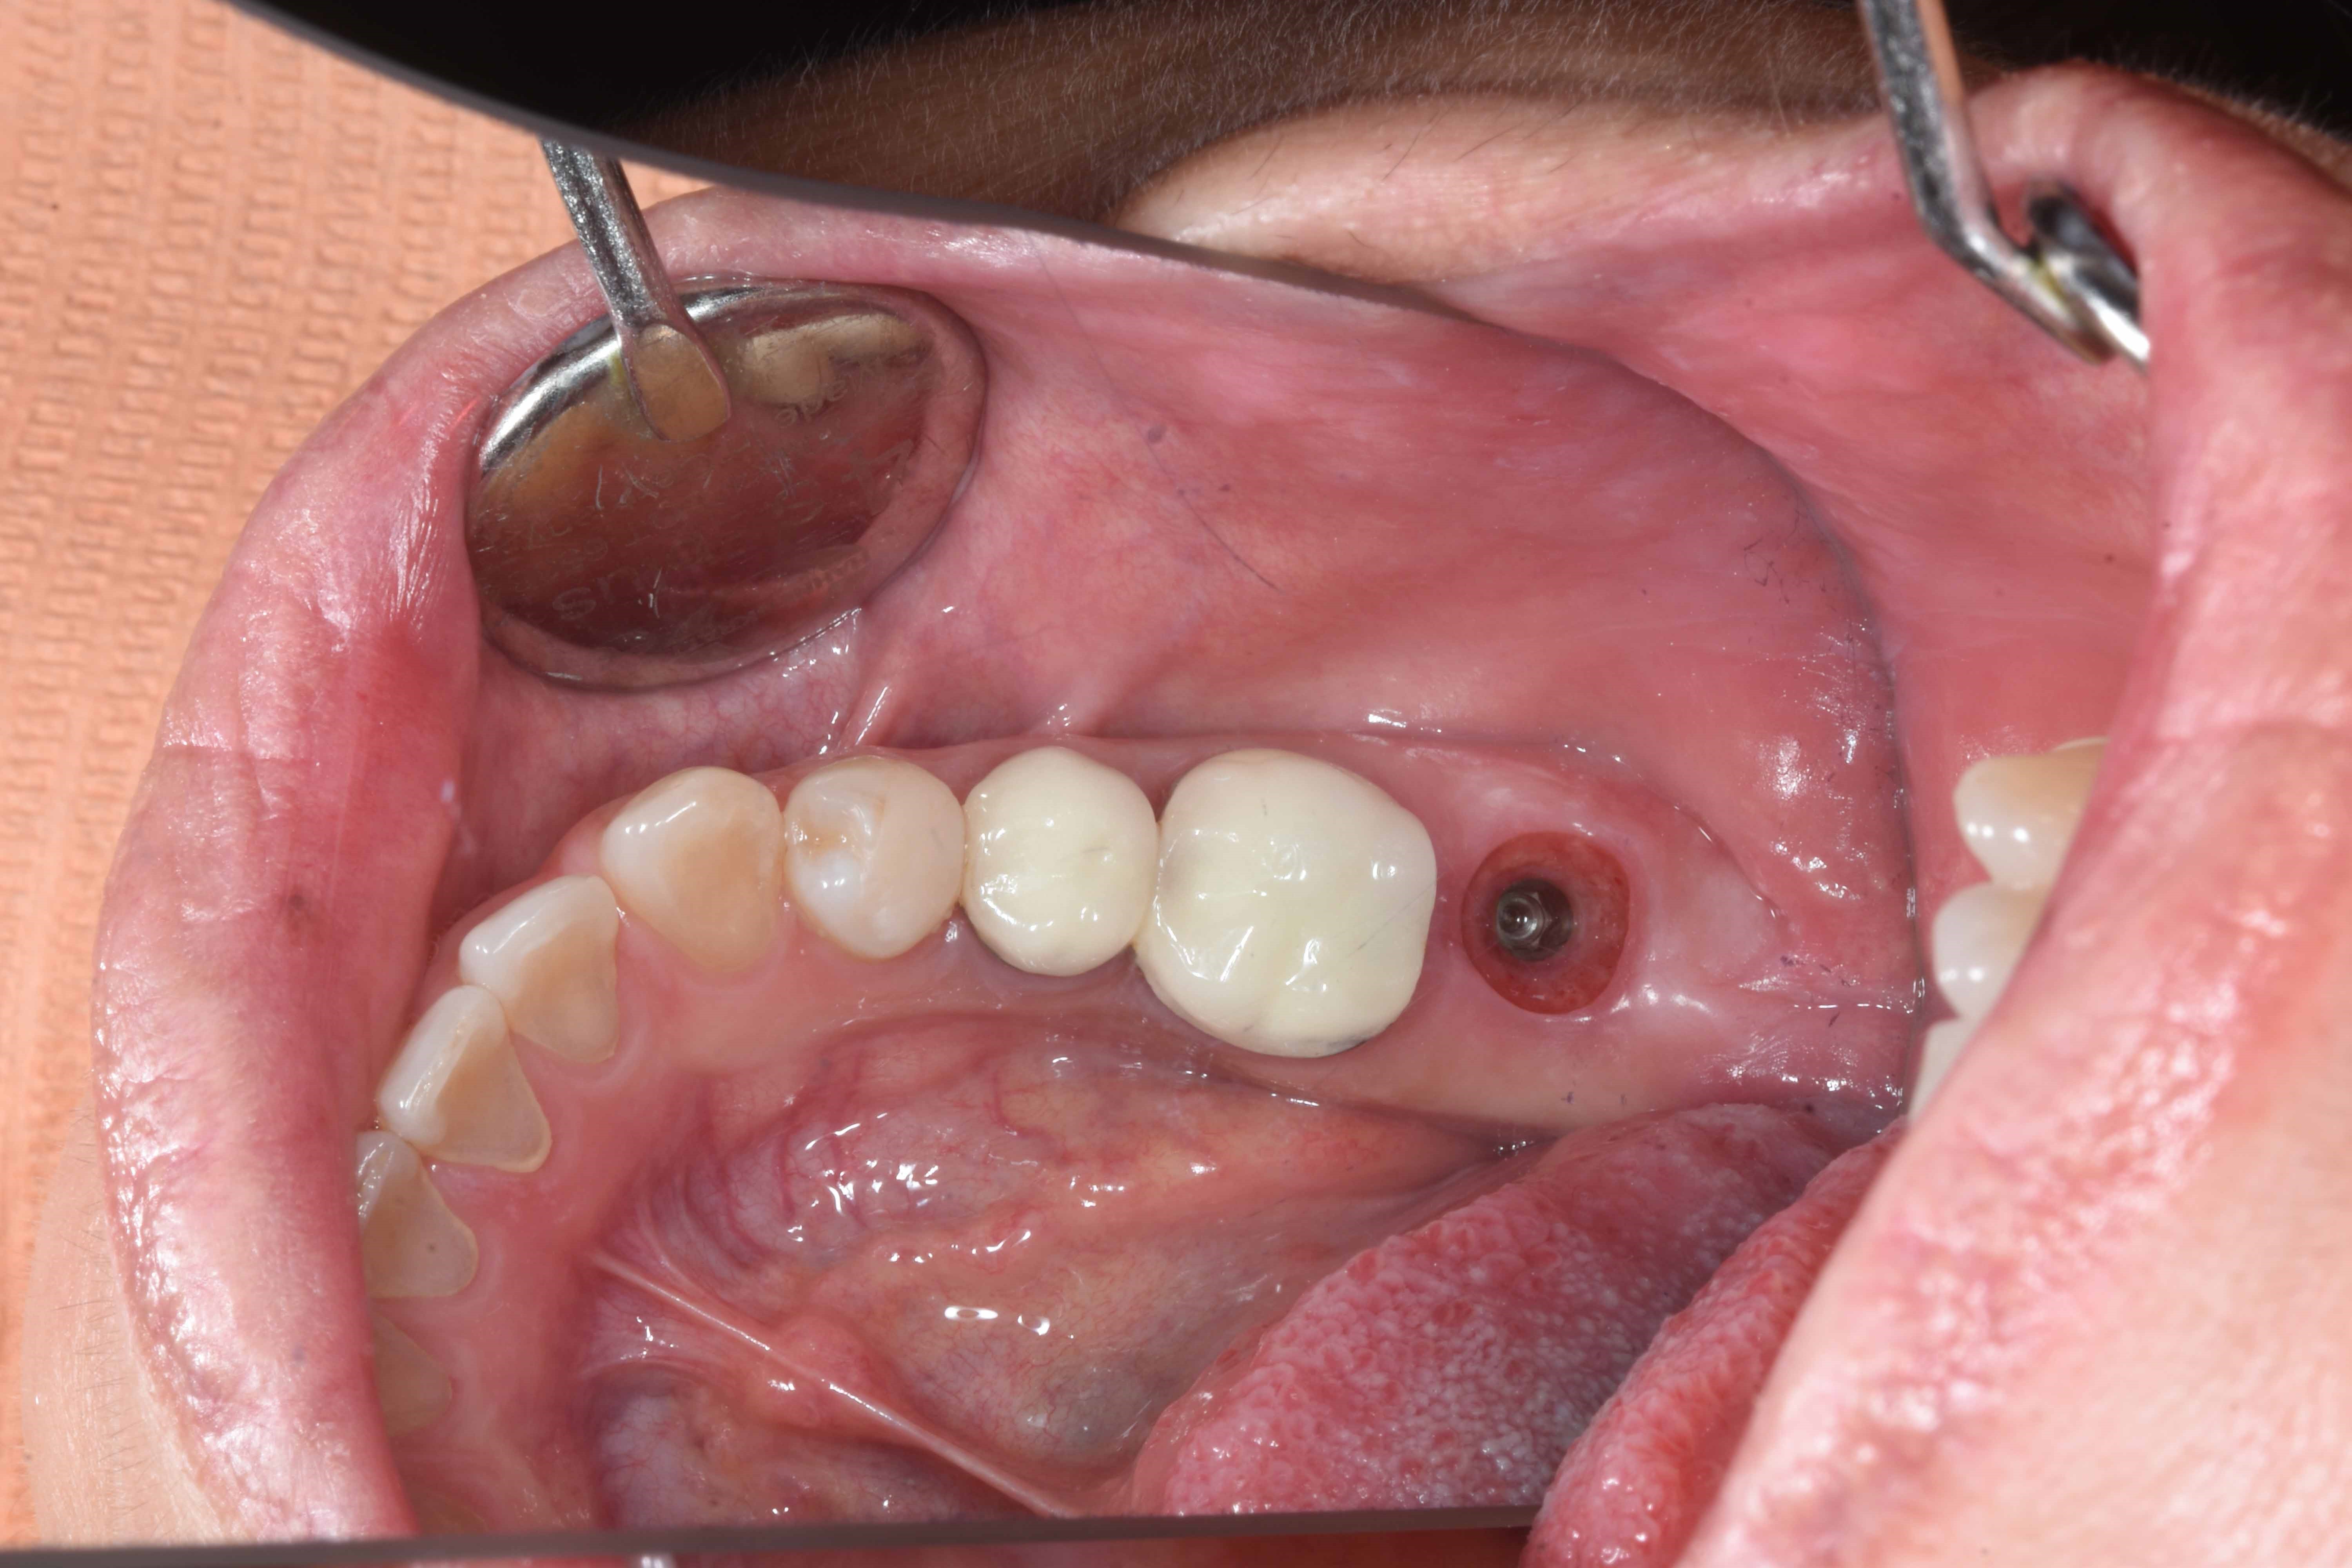

案例一

立即拔除,當天完成植牙手術,並鎖上癒合螺帽

2-3月癒合,取下癒合螺帽,透過數位口掃至技公所製作假牙

7-10天完成假牙,試戴、調整咬合高度並鎖上

封填,完成